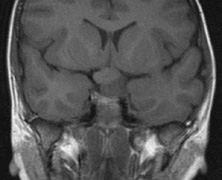

Optic nerve gliomas may involve the optic chiasm and be associated with endocrine disorders or nystagmus.68–70 Surgical excision of chiasmal gliomas (Fig. 6) carries a high risk of visual loss. Invasion of the hypothalamus or the third ventricle carries a poor prognosis, with greater than 50% 15-year mortality rate.71 One review of radiation treatment for chiasmal gliomas collated data from small case series and found no significant long-term improvement in visual function, progression, or mortality with radiation treatment.71 Other reports suggest that radiation doses over 4500cGy improve symptoms and slow progression of chiasmal gliomas over several years.72 Adequate tumor coverage by radiotherapy results in irradiation of normal brain and nearly all children need hormone replacement.73 Chemotherapy is an alternative.74,75

|